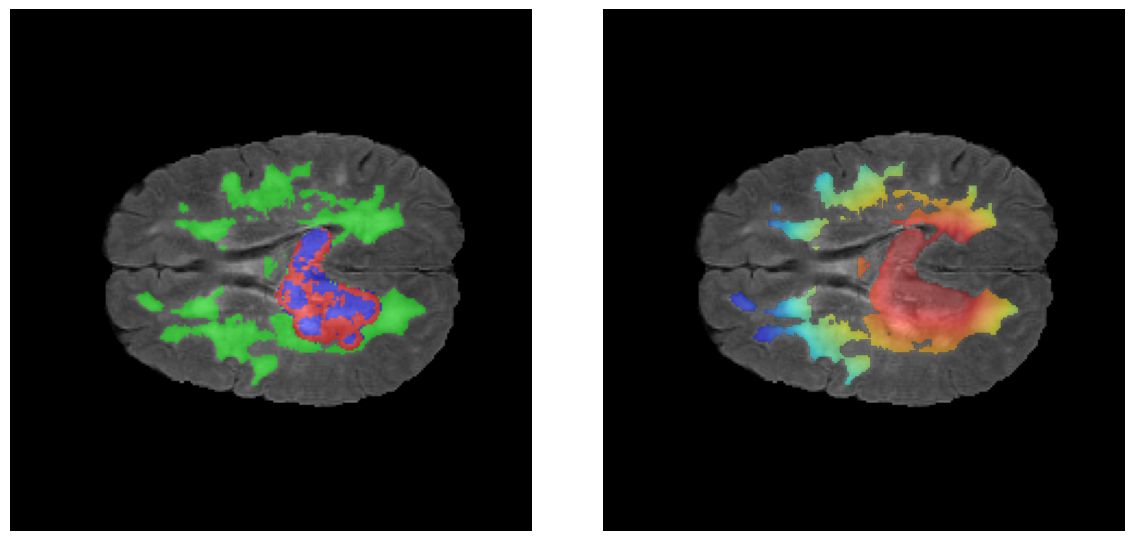

Mapas de Explicabilidad (Grad-CAM++)

Visualización de las regiones de atención del modelo que validan su razonamiento clínicamente relevante

Ejemplos HGG - Atención en Núcleo Necrótico y Tumor Realzado

HGG Grad-CAM++ 1 HGG Grad-CAM++ 2 HGG Grad-CAM++ 3 HGG Grad-CAM++ 4 HGG Grad-CAM++ 5 HGG Grad-CAM++ 6

Los heatmaps muestran que el modelo concentra su atención en las regiones de Tumor Realzado (rojo) y Núcleo Necrótico (azul), características patológicas clave de los gliomas de alto grado.

Ejemplos LGG - Atención Difusa en Edema Peritumoral

LGG Grad-CAM++ 1 LGG Grad-CAM++ 2 LGG Grad-CAM++ 3 LGG Grad-CAM++ 4 LGG Grad-CAM++ 5 LGG Grad-CAM++ 6

Para casos LGG, la atención del modelo es más difusa y se concentra principalmente en la región de Edema Peritumoral (verde), consistente con la naturaleza más infiltrativa y menos agresiva de estos tumores.

El análisis Grad-CAM++ reveló que el modelo desarrolla automáticamente la capacidad de localizar las regiones tumorales. Para casos HGG, la atención se alinea fuertemente con las regiones de Tumor Realzado (ET) y Núcleo Necrótico (NCR). En contraste, los casos LGG muestran atención más difusa, principalmente concentrada en la región de Edema Peritumoral (ED), lo cual es consistente con la patofisiología conocida de los gliomas.